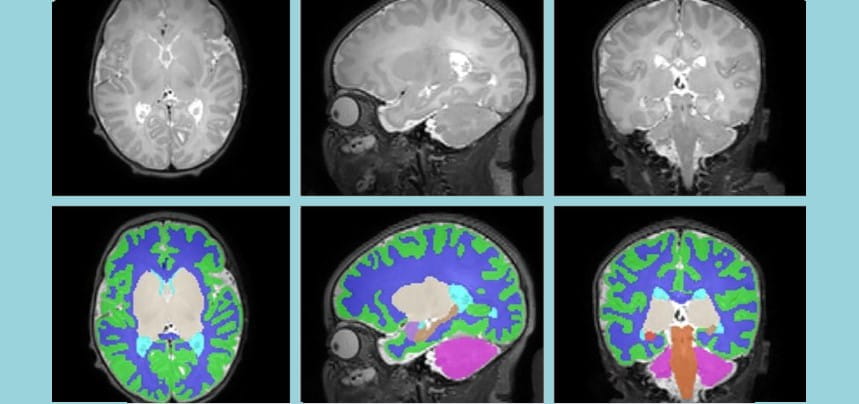

The research I do focuses on how the newborn brain can bounce back from insults including brain injury and substance exposure. I am also interested in using MRI as a tool to predict and improve the outcomes of term and preterm babies with brain injury. I am honored every time someone is interested in the research my team is doing.

Follow-up outcomes; advanced neuroimaging to predict outcomes in infants with brain injury and prenatal substance exposure

In Utero Opioid Exposure Impacts Fetal Brain Size and Development